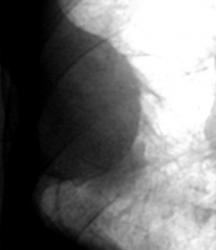

На цифровой флюорограмме, произведенной в прямой стандартной проекции справа паракостально определяется полуовальная тень, широким основанием интимно примыкающая к грудной клетки – иллюстрации 2, 3. Тень значительной интенсивности, однородной структуры с довольно ровным и четким контуром. Определяются линейные тяжевидные структуры отходящие от контура тени в окружающую легочную ткань – шварты.

Данная фокусная тень с грудной стенкой образует «тупые углы». Справа над диафрагмой определяется снижение прозрачности легочной ткани значительной интенсивности, однородной структуры с косой верхней границей. Иллюстрация 1 – флюорограмма пациента, проведенная за 6 месяцев до этого обращения с профилактической целью. Скиалогическая картина фиксирует возрастные изменения.